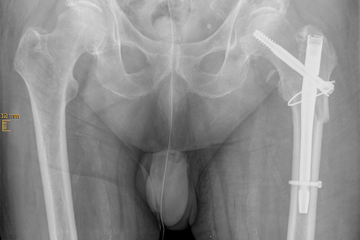

Ursache für komplexe Knochenbrüche wie Hüft- oder Schulterfraktur ist eine reduzierte Knochenqualität. Die häufigsten dieser Verletzungen sind die handgelenknahe Speichenfraktur (Radiusfraktur), die hüftgelenknahe Oberschenkelfraktur (mediale/pertrochantäre Fraktur), die Schulterfraktur (proximale Humerusfraktur) oder die Fraktur eines oder mehrerer Wirbelkörper.

Diese Verletzungen können für einen älteren Menschen teilweise gravierende Folgen haben. Eine Schenkelhalsfraktur kann bei einem älteren Patienten mit dem plötzlichen Verlust seiner Selbstständigkeit und Mobilität verbunden sein und eine Vielzahl anderer Komplikationen nach sich ziehen. Eine drohende temporäre oder dauerhafte Pflegebedürftigkeit kann sich daraus entwickeln.

Der verletzte ältere Mensch benötigt oft ein komplexes Behandlungsregime, das seine Unfallfolgen, die schlechte Knochenqualität (Osteoporose) und die Nebenerkrankungen (Multimorbidität) gleichermaßen einschließt.